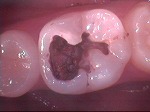

ドックスベストセメント

~初診~

~歯髄に近い深い虫歯~